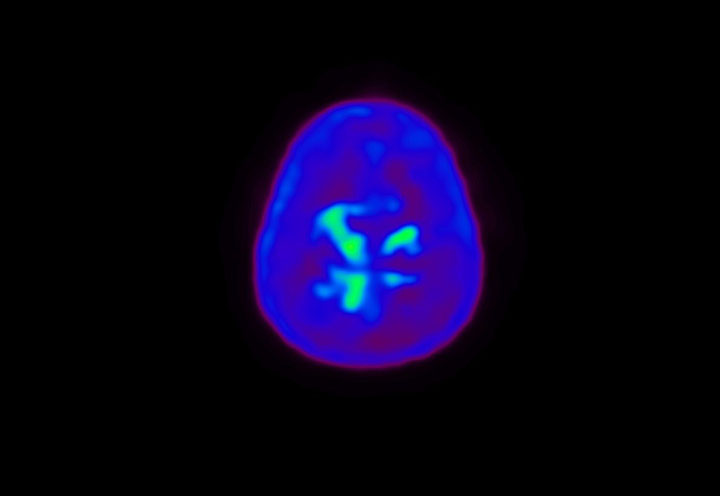

Head / Case4 : Amyloid

Axial

Courtesy : Kindai University Hospital

- Imaging protocol

- Injected dose: 3.21 MBq/kg, 18F-Flutemetamol

- Uptake time: 100 minutes

- Scan time: 20 minutes